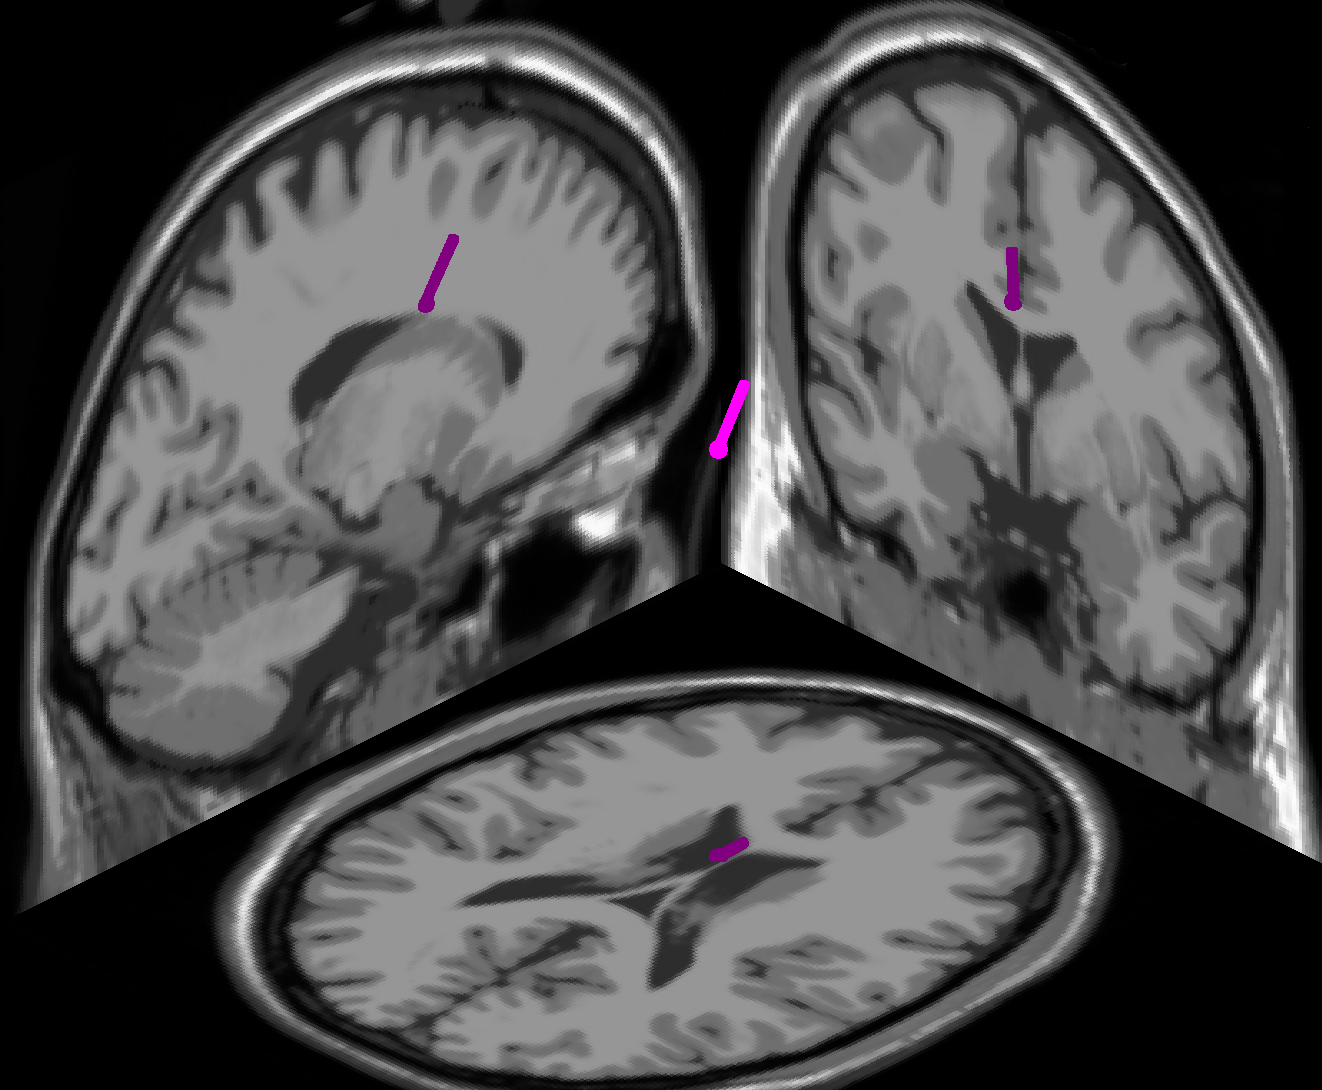

We first high-pass filtered the resting-state data of each subject at a cut-off frequency of 3 Hz, and then performed a group-wise ICA on the combined resting-state data of all subjects. We chose the SOBI algorithm [2] for this purpose, as ICA algorithms based on second-order statistics have been shown to outperform methods based on higher moments in group-wise analyses [21]. We manually inspected the topography and spectrum of every resulting independent component (IC) and rejected all ICs as non-cortical that did not exhibit a clear dipolar topography [9]. The topographies and equivalent dipoles of the six cortical ICs that we retained for further analyses are shown in figure 3. Equivalent dipole locations were derived with a three-shell spherical head model with standardized electrode locations, using the EEGLAB toolbox [8]. We note that ICs 1 and 2, located in sensorimotor and occipital cortex, represent sensorimotor and low-level visual processes, respectively. In contrast, ICs 3, 4 and 5, located in precuneus, in the anterior cingulate, and at the intersection of cuneus and precuneus, respectively, are generated in cortical areas linked to fronto-parietal attention networks [5]. IC 6 appears to represent a sub-cortical source.

Refer to caption

(a) IC 1, RV 5.88%

(b) IC 2, RV 3.28%

(c) IC 3, RV 4.39%

(d) IC 4, RV 3.25%

(e) IC 5, RV 3.07%

(f) IC 6, RV 1.88%

Figure 3: Topographies and equivalent dipole locations of the six cortical ICs from the group-wise ICA. The residual variances of the equivalent dipole fits are denoted by RV.